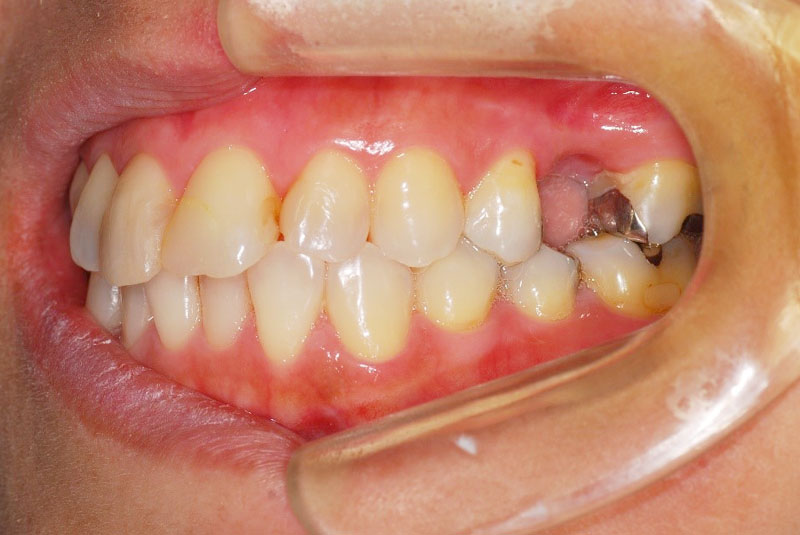

臼歯1本欠損症例

-

術前

術後

- 患者

- 40代女性

- 主訴

- 歯がないところに歯を作りたい。

左上に1本だけのいればをつかっていたが、両側の歯を削らないで固定式の歯を入れて噛めるようにしたいとのことでご来院された患者さんです。臼歯の1本欠損はブリッジで対応されることが多いですが、最近は両側の歯に負担をかけたくないとのことでインプラントを検討される方が増えてきました。

- 治療費

- インプラント検査 3.3万円

臼歯部インプラント手術 22万円

アバットメント 7.7万円

フルジルコニアクラウン 11万円

合計44万円

- 治療回数・期間

- 6回 6か月

- リスク

- 術後の疼痛、出血、腫脹

術後感染

インプラント脱落

インプラント周囲炎

上部構造破折